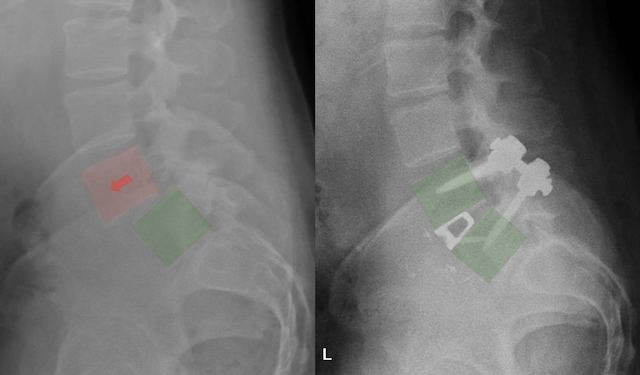

Comparison of two spinal X-rays, one with medical implants and markers highlighting features.

X-ray images of the lower spine showing a surgical procedure with hardware, such as screws and rods, implanted in the lumbar vertebrae.